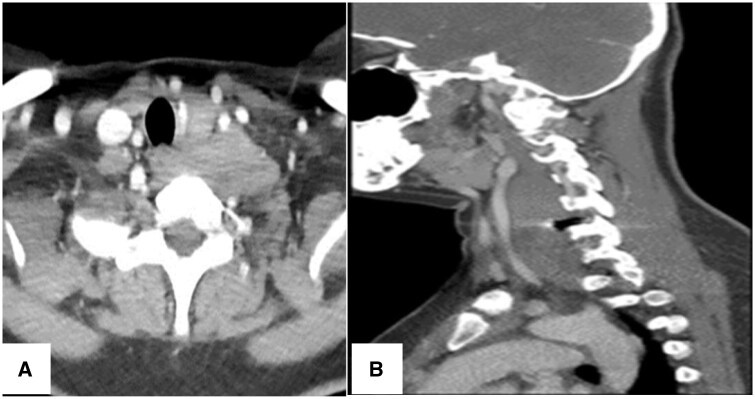

Desmoid tumours are rare benign tumours that show locally aggressive and invasive features leading to potential complications. They can be quite challenging for the treating surgeon if they occur adjacent to neurovascular structures. The aetiology of these tumours is still unclear, but the incidence is higher in females and in patients with a history of trauma or surgical procedures, raising the possibility of genetic and hormonal factors as well as post-traumatic or post-operative inflammatory changes promoting the formation of desmoid fibromatosis. We report a case of a 34-year-old Asian female who presented to our hospital with a history of difficulty in swallowing due to an enlarging lump on the left side of her neck. Patient had a past medical history of previous cervical spinal disc surgery due to a herniated disc. Diagnostic imaging showed a large soft tissue mass centred between the left common carotid artery and the cervical vertebrae displacing the trachea and oesophagus to the right side. A biopsy was obtained, and histopathological examination was suggestive of a desmoid tumour. The patient underwent surgical resection of the tumour but returned later with recurrence and had to undergo the surgery again to achieve full cure.